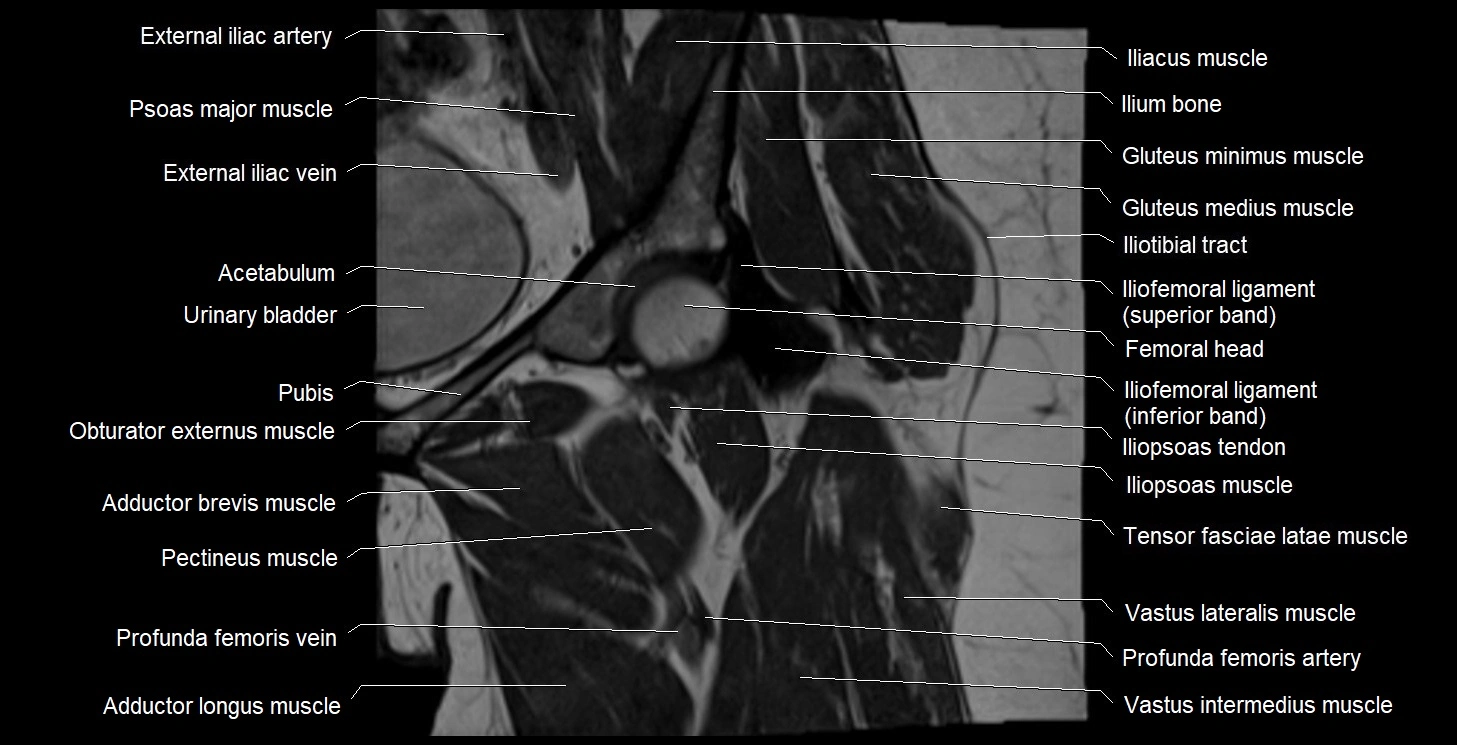

- Acetabulum

- Deep femoral vein (profunda femoris vein)

- External iliac artery

- External iliac vein

- Gluteus minimus muscle

- Gluteus minimus tendon

- Head of femur

- Iliofemoral Ligament inferior band (vertical band, medial band)

- Iliofemoral Ligament superior band (transverse band, lateral band)

- Iliopsoas muscle

- Iliopsoas tendon

- Iliotibial tract

- Pectineus muscle

- Psoas major muscle

- Tensor fasciae latae muscle

- Urinary bladder

- Vastus intermedius muscle

- Vastus lateralis muscle